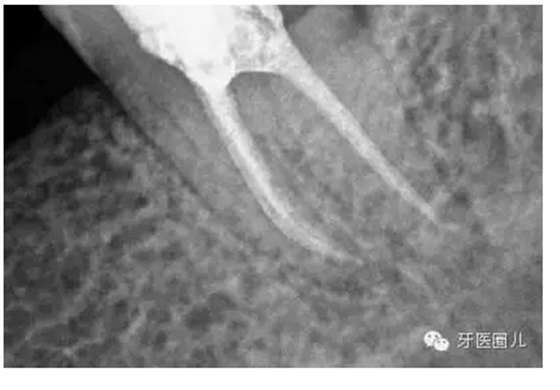

這三個病例采用protaper器械,最后一個病例有不足,遠(yuǎn)中舌根根尖2mm有一個嚴(yán)重的向上彎曲,預(yù)備和充填時沒有到達(dá),術(shù)前評估和術(shù)中評估時覺得這個病例難度超過了我的操作范圍,但是患者沒有精力選擇更好的醫(yī)院,我于是和他講明狀況盡量做到我能做的了